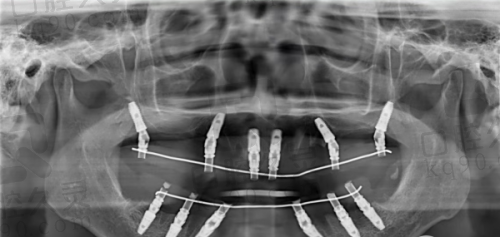

到了丽水亮贝美口腔医院,前台工作人员热情地接待了我,引导我填写了基本信息,并带我去见了医生。医生非常和蔼可亲,详细询问了我的牙齿缺失情况、过往病史等。然后安排我进行了一系列的口腔检查,包括口腔CT、X光等。检查过程中,医护人员操作熟练,动作轻柔,没有让我感到任何不适。通过这些检查,医生全方面了解了我的口腔骨骼、牙周组织等情况,为后续的种植牙手术方案制定提供了正确的依据。

丽水亮贝美口腔医院的单颗种植牙技术有着特别多特色。首先,医院采用的是数字化种植技术,通过精良的设备可以精细地定位种植体的位置和深度,大大提高了手术的成功几率。其次,医院的医生团队会根据患者的口腔情况和需求,制定个性化的种植方案,确保种植成效既美观又实用。另外,医院使用的种植体都是经过严格筛选的优质产品,质量有保护。就像净网行动会筛选出虚假信息一样,医院也会筛选出更适合患者的种植体。